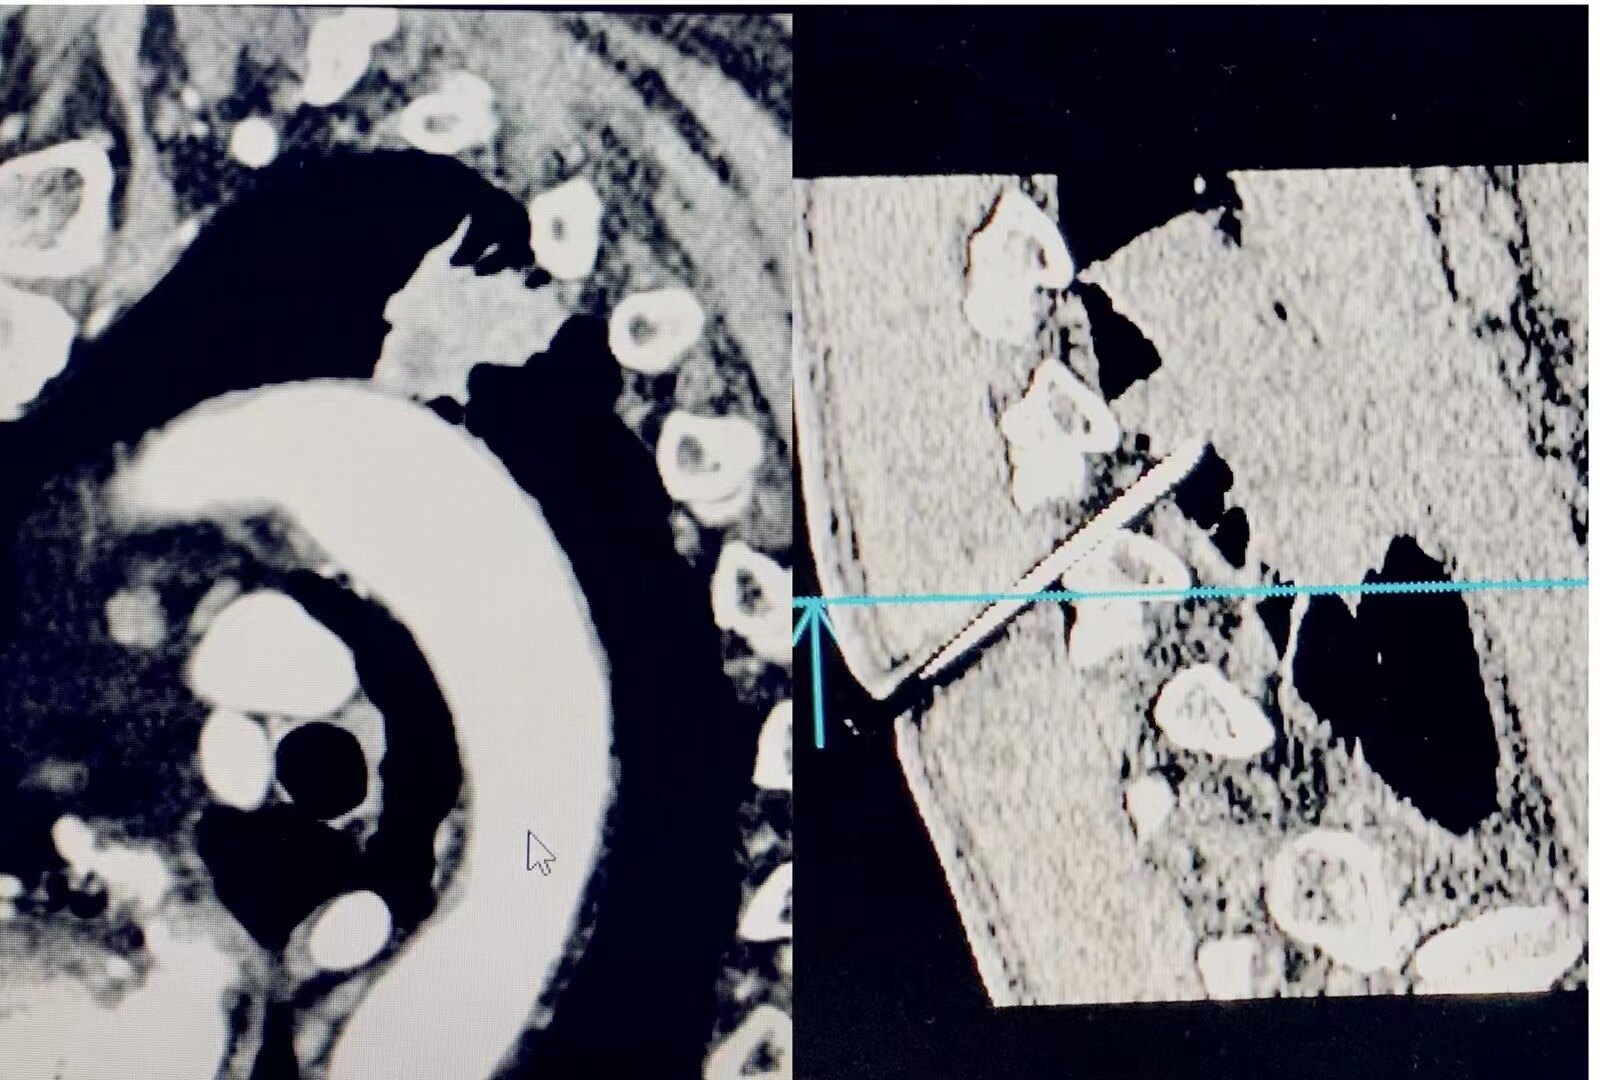

经过严密术前准备,缜密的穿刺入路选择, 最后肺穿刺✅顺利完成,肺癌确诊,完成靶向基因、免疫检测,进入治疗阶段......

杜学奎主任CT下肺穿刺

近期2例高风险肺穿刺。胸主动脉弓、降主动脉旁(人体最粗大,血管压力最大的血管)